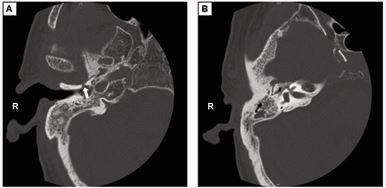

An erythrocyte sedimentation rate of 54 mm/h was detected, with normal results for the complete blood count and C-reactive protein. A computed tomography (CT) scan showed low-density shadows in the right tympanic cavity and mastoid process, bony erosion in the anteroinferior wall of EAC leading into the mandibular fossa, and massive low-density shadows around the condyle [Figure 1]. Magnetic resonance imaging (MRI) with contrast exhibited enhancement around the right TMJ and adjacent muscles [Figure 2].

Figure 1 The computed tomography scan of the patient. (A) The bone destruction formed a sinus (the arrow) from the anteroinferior wall of EAC to the mandibular fossa. (B) Inflammatory tissue filled the tympanic sinus, tympanum and mastoid process.

Septic arthritis of the TMJ is known as a rare complication of otitis media. Potential routes of direct dissemination include opened squamotympanic fissures, incomplete ossification of tympanic plate, Santorini’s fissures (natural openings in the lateral cartilaginous auditory canal), Huschke’s foramens [5,6]. Tuberculosis of the temporomandibular joint and parotid secondary to TBOM was reported by merely one study [7]. In that case, a sinus from the anterior wall of external auditory canal to the TMJ was observed. Similarly, in our study, the infection perhaps spread to TMJ via a sinus from the anteroinferior wall of EAC which was observed in the CT scan.